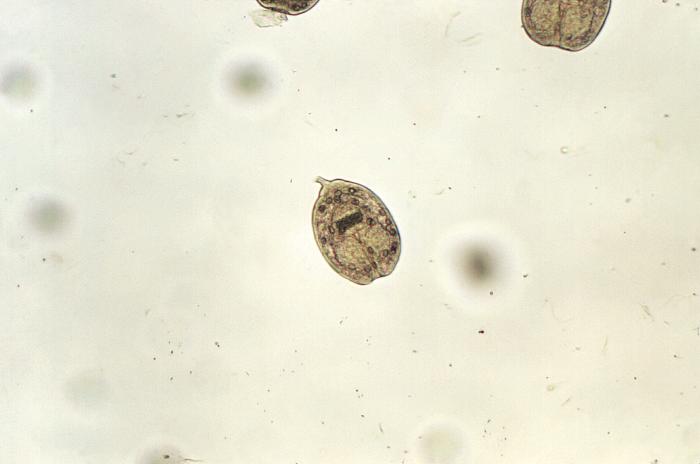

Los endoparásitos se caracterizan por ser parásitos que desarrollan parte o todo su ciclo vital en el interior del huésped. Se incluyen los protozoos (unicelulares) y los helmintos o gusanos (pluricelulares), que a su vez se dividen en dos filos: los nematodos y los platelmintos. Tienen ciclos de vida complejos, alternando fases de vida libre y parasitaria.